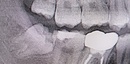

10代男性 横に生えた状態で埋まっていた親知らずを抜いて「智歯周囲炎」を改善した症例

名古屋 市 天白区の歯医者・歯科・親知らずの抜歯治療・歯科口腔外科のイナグマ歯科です。院長 ...